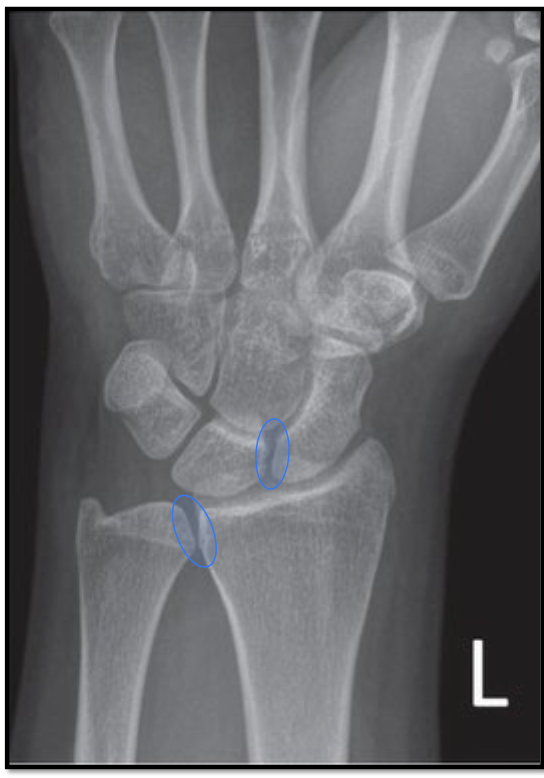

What is the positioning fault?

How would you fix it?

A

• scapholunate joint is closed (obliqued)

• trapezoid and trapezium are seperated

• thumb is away from IR